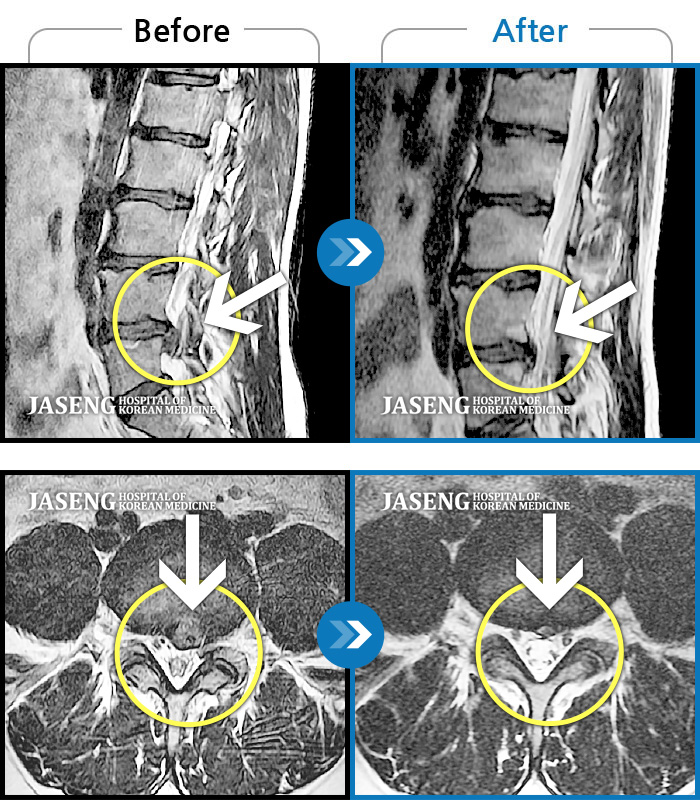

처음엔 이곳저곳 아파서 확실하게 어디가 아팠는지 몰랐는데 사고 후 일주일쯤 될 무렵 MRI촬영후 정확하게 진단을 받았습니다

허리디스크 2단계(초기) 진단을 받긴 했으나 다행히 근육량이 많아 모르고 살았는데 사고로 인해 디스크에 상처가 생겨 힘든 나날을 보내고 있습니다

70대 어머니가 디스크파열로 수술을 당장해야한다는 큰병원의 권유를 뒤로하고 자생을 결정하고 엄봉군원장님을 만났습니다. 두달여 치료받고 많이 호전되었고 갈때마다 진심을 다하시는 원장님으로 인해 정서적인 치료도 받고 있답니다 앞으로도 잘 부탁드립니가!!